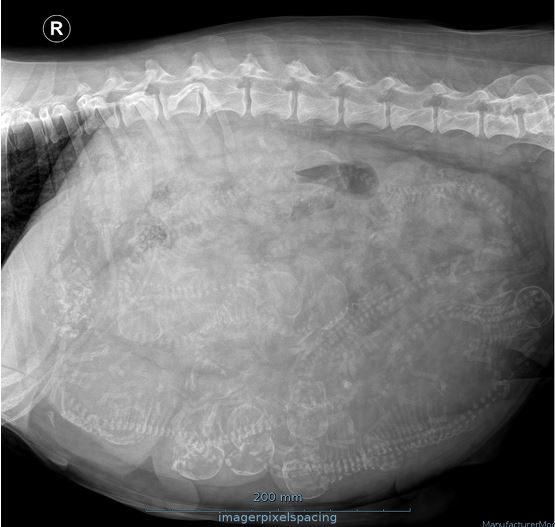

Flicka er blevet røntgenfotograferet torsdag d 22. maj og det tegner til at blive et stort kuld. Dyrlægen mener der er 12 dejlige vidundere derinde.